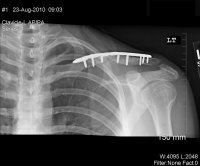

Xrays

Update: August 23, 2010

Saw the Doc again, he's pleased with the results, but it's just going to take more time. If you look at the x-rays you can see that the void is closing, slowly.

He seemed very confidant that it should be ok by T-Day, will know more in 6 weeks.